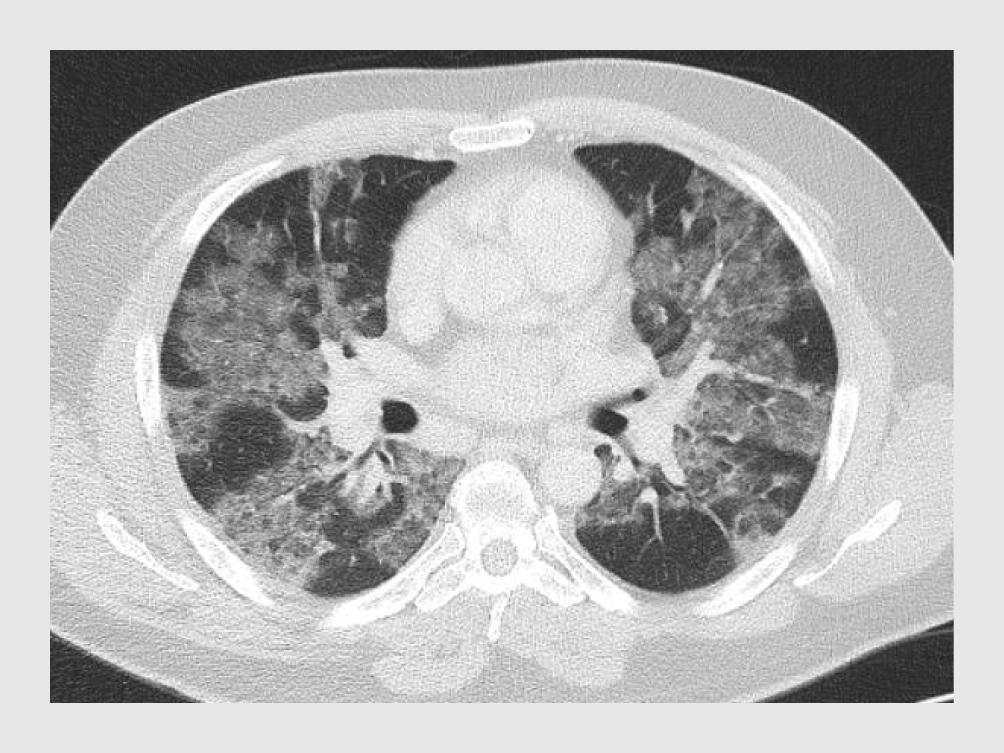

Gezien de afwijkingen op de thoraxfoto wordt een CT-scan vervaardigd. Deze laat beiderzijds diffuus verspreide matglasafwijkingen zien, evenals mediastinale lymfadenopathie (figuur 2).

Figuur 2

CT-scan van een patiënt met COVID-19

Figuur 2 | CT-scan van een patiënt met COVID-19

CT-scan van de thorax van patiënt A (transversale coupe). Beiderzijds zijn diffuus verspreide matglasafwijkingen te zien, evenals mediastinale lymfadenopathie.